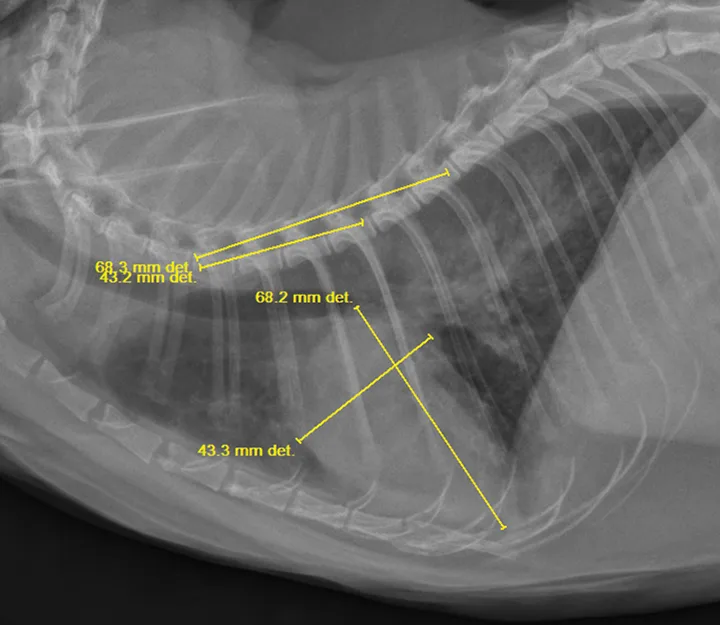

Left atrial enlargement is typically present in both cats and dogs with L-CHF. In dogs, left atrial enlargement typically appears in radiographs as a rounded increased opacity caudal to the carina in the perihilar region on the lateral projection. (See Figure 1A.) Generalized cardiomegaly is identified by measuring vertebral heart score (VHS).3,5 (See Figure 3.) In cats, both generalized cardiomegaly and left atrial enlargement are more difficult to assess because of their more subtle radiographic changes; they are characterized by a VHS score greater than 8 and the presence of a valentine-shaped heart on the VD/DV projection, respectively. However, normal left atrial size on thoracic radiography does not rule out the presence of L-CHF in dyspneic cats.1 Once acute L-CHF has been identified and treated, evaluation by a cardiologist is recommended, but stabilization of the patient is the first priority.

A lateral radiograph of a canine thorax shows the ribcage and heart silhouette, with measurements indicated in yellow lines. The dimensions of 68.3 mm and 43.2 mm highlight specific areas of interest for clinical evaluation.

FIGURE 3

VHS of 10.5 in a cat. Normal VHS for cats and dogs is less than 8.0 and less than 10.5, respectively. Note the diffuse interstitial-to-alveolar lung pattern, which most likely represents cardiogenic pulmonary edema.